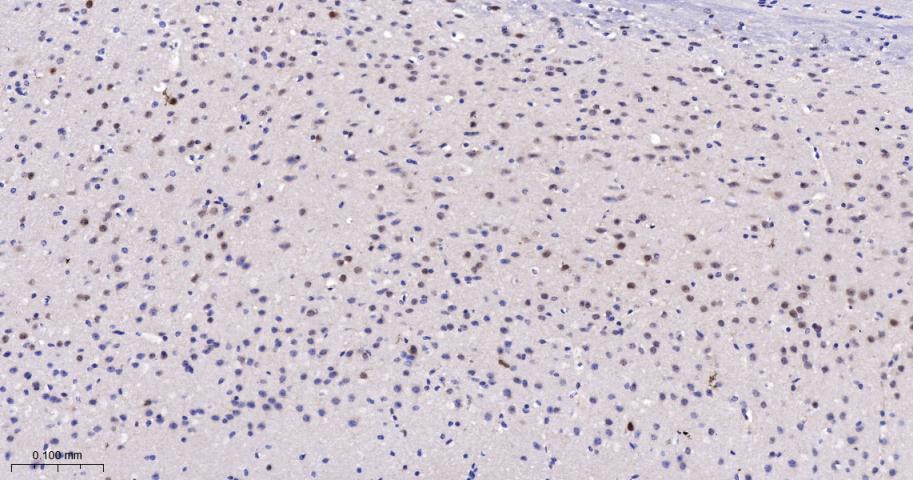

Paraformaldehyde-fixed, paraffin embedded Rat Cerebrum; Antigen retrieval by boiling in sodium citrate buffer (pH6.0) for 15 min; The section was incubated with PRMT5 Monoclonal Antibody, Unconjugated (bsm-60525R) at 1:200 overnight at 4°C, followed by conjugation to the bs-0295G-HRP and DAB (C-0010) staining.

Paraformaldehyde-fixed, paraffin embedded Mouse Cerebrum; Antigen retrieval by boiling in sodium citrate buffer (pH6.0) for 15 min; The section was incubated with PRMT5 Monoclonal Antibody, Unconjugated (bsm-60525R) at 1:200 overnight at 4°C, followed by conjugation to the bs-0295G-HRP and DAB (C-0010) staining.